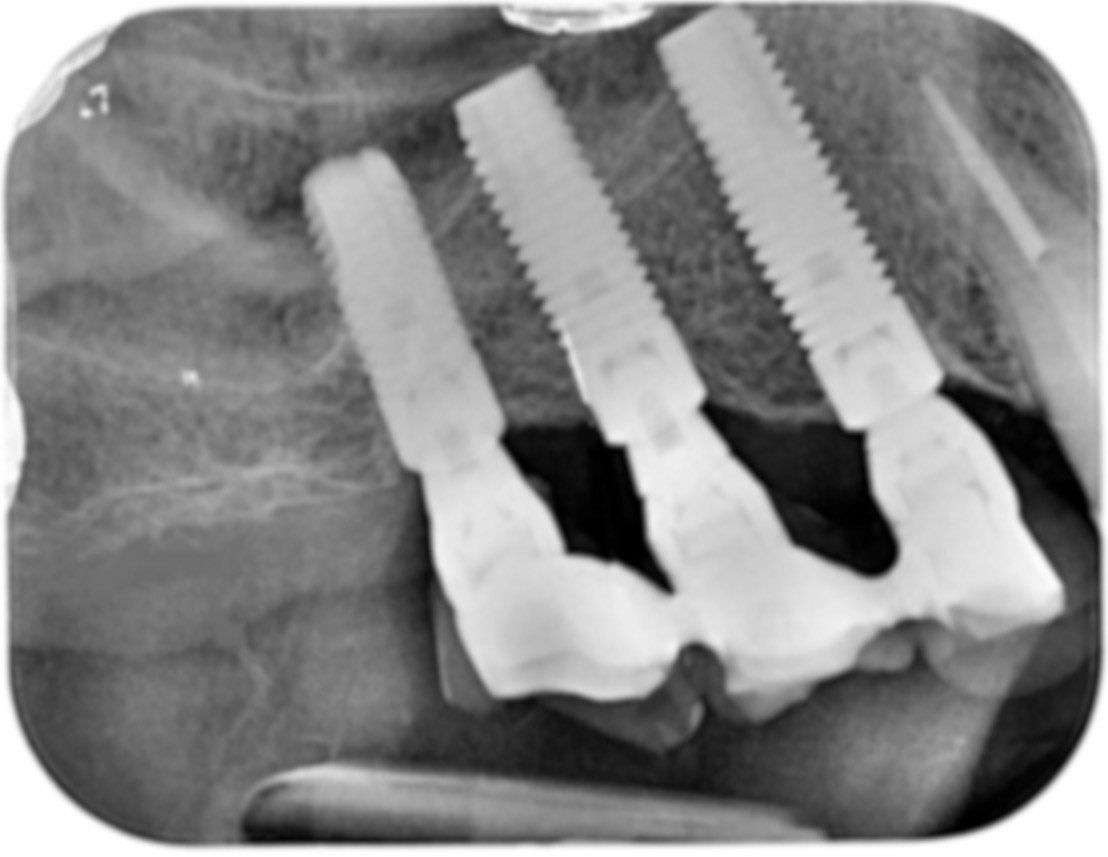

La panoramica dimostra l’esiguità del triangolo retrocanino che non può pertanto essere utilizzato per l’inserimento di due impianti. L’area posteriore rivela un’atrofia ossea pronunciata che richiede un rialzo di seno con innesto di osso del paziente (autologo) che verrà prelevato dal ramo mandibolare

Dopo sei mesi dall’innesto vengono inseriti gli impianti e dopo ulteriori sei mesi vengono applicati i denti in ceramica.